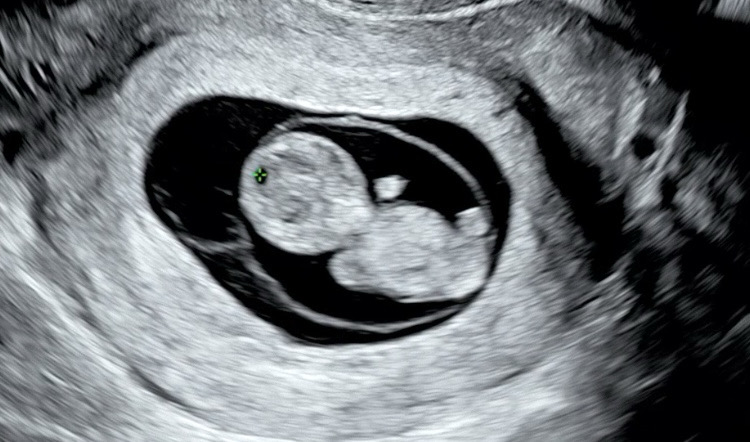

오늘로 딱 10주0일이에요! 애기 크기는 2.88cm로 심박은 175bpm 인데 크기로 봤을땐 주수가 9주5일로 이틀 차이나요! 다른분들은 10주 되면 애기가 평균 3.1cm 이상 이라는데 저는 조금 작은것 같아서요!ㅠㅠ 선생님은 이틀차이는 무시해도 된다고 하시는데 괜히 작은 일에도 걱정되네요~~~ 그나마 다행이도 애기 심박은 우렁차게 잘 뛰고 꼼지락 꼼지락 잘 놀고있었어요😝